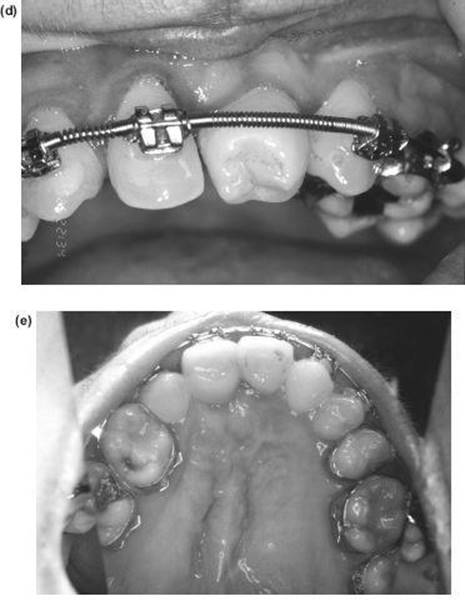

The Lower Labial Segmental Osteotomy (Kole Subapical Osteotomy)

Although this operation may be used to move the dentoalveolar segment in almost any direction permitted by the angulation of the teeth, it should not be used as an alternative to presurgical orthodontics and is less useful and more difficult than the anterior mandibulotomy If carried out as a single procedure, intermaxillary fixation is not required. The alveolar segments can be secured with bone plates plus:

1. An arch bar, the best being a cast chrome cobalt bar designed on the surgical planning model.

2. An orthodontic arch wire fitted intraoperatively or more readily a heavy (1 mm) supplemental arch wire fitted into distal buccal tubes and ligated to the segment and the adjacent teeth. The segments are localised by a postoperative wafer and bone plates below, which are not enough without the dental control to prevent displacement.

Technique

Downward and posterior movements (Figure 9.8)

1. A premolar is carefully extracted bilaterally to create space for a distal movement. For vertical movements without extractions it is imperative to confirm that there is sufficient bone between the roots of the teeth. The orthodontist can achieve increased separation with a fixed appliance.

2. Whichever incision is used (see below), extend the lips, dry the mucosa, and mark it out with a pen and Bonney's blue.

3. The procedure is done with a curved incision starting below the papilla distal to the site of the vertical bone cut (Figure 9.8a) at the reflection of the sulcus mucosa. The blade is then taken very superficially through the mucosa along the inner aspect of the lip anterior to the sulcus, returning in an arc of a circle to the equivalent point on the opposite side. Finger dissection with a gauze swab will reveal the three terminal branches of the mental nerve. These must be exposed by dissecting backwards to the foramen with scissors. The anterior labial section of the incision can now be deepened with a blade obliquely downwards to bone approximately halfway between the gingival margin and lower border of the mandible. This skirt of mucosa facilitates suturing and also provides a good seal if bone chips are being inserted.